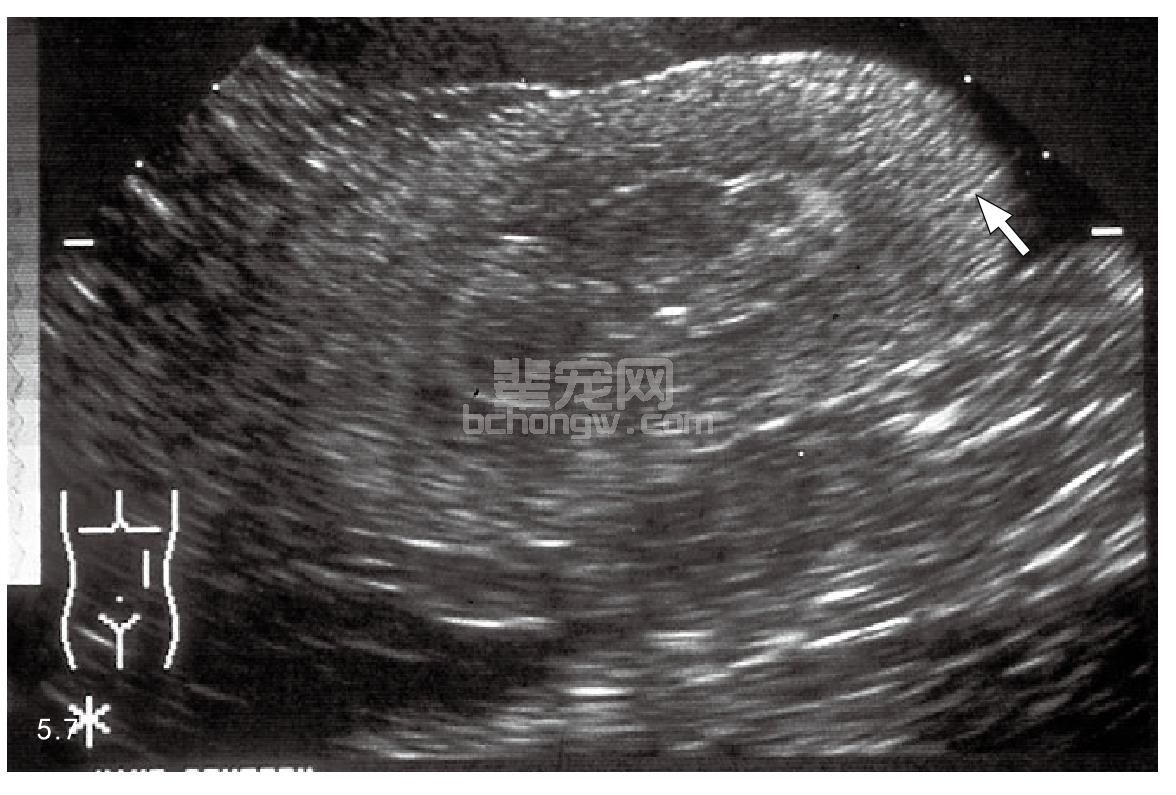

为了提供合适的治疗和准确的预后,必须鉴别急性肾衰竭和慢性肾衰竭(CRF)(表5.2)。当发生肾毒素性疾病,血清肌氨酸酐和BUN(尿素)水平迅速升高时很容易诊断为ARF。然而,相对突发临床症状的氮质血症有时也与CRF有关。患有ARF的动物通常少尿,但是温和形式的发病和肾毒素会出现多尿,如氨基糖甙类药物、两性霉素B和血钙过多时。ARF和CRF的血浆钠和钾的主要变化相似。患有ARF的动物不会发生贫血,除非有其他的原因在当时引发出血。尿分析显示轻微的蛋白尿并伴有尿沉渣,包括很多管型和脱落的上皮细胞。二水合草酸钙和/或一水合结晶尿与乙二醇中毒有关(图5.6)。X线学检查可以确定肾脏是正常大小还是变大了,造影检查有助于确定尿道的损伤或者狭窄部位。超声检查也有助于诊断,如乙二醇中毒时回声增强(图5.7)。在许多情况下,肾组织活检有助于区别ARF还是CRF,并能确定肾脏损伤的严重程度,由于有很高的出血性危险,所以肾脏活组织检查并不是常规的检查项目。

图5.7 超声波检查乙二醇中毒病犬的肾脏,在肾脏皮质区回声增强(箭头所指)。